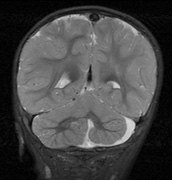

CNS hemangiomas are the most common tumor of VHL, affecting 60% to 80%, with a predilection for the cerebellum and spinal chord. An enlarging cystic component is a frequent finding in symptomatic tumors. Patients typically present in their early 30s; headaches or neck pain in affected individuals should not be ignored.172,173 On microscopy, CNS hemangiomas resemble retinal capillary hemangiomas. Their malignant potential is low.174 The treatment is surgical (Fig. 17, A and B).13

Fig. 17. Images from a 13-year-old boy with Von Hippel-Lindau syndrome. (a) Coronal postcontrast T1-weighted imaging reveals a cystic lesion with an enhancing nodule at the pial surface typical of a hemangioblastoma. (b) A second solid enhancing hemangioblastoma is seen at the craniocervial junction on a sagittal postcontrast T1-weighted image. (c) Associated cystic lesions (arrows) are seen within the pancreas.

Pancreatic lesions may be nonsecretory (most commonly cysts or cystadenomas) or secretory (islet cell tumor).179 In one study of 52 patients, 56% (29 patients) were found to have pancreatic lesions. The majority (19 of 29) had cystic changes only (Fig. 17C). Pancreatic lesions were the only abdominal manifestation of disease in 6 of 52 patients.180 In a separate study, pancreatic cysts did not show significant progression on follow-up examinations over an average period of 5 years.181 Like pancreatic cysts, islet cell tumors appear to be frequently asymptomatic.182